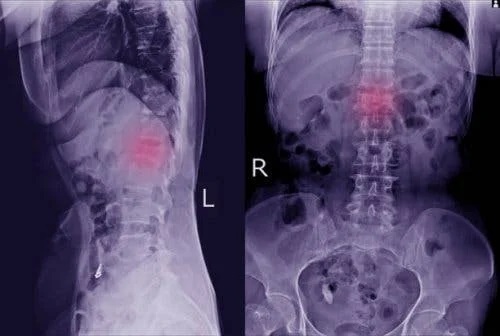

Aceste manifestări fizice sunt ușor de trecut cu vederea. Acordă-le atenție și mergi la medic pentru a efectua unul dintre principalele teste care permit detectarea bolii: radiografia cu raze X. În acest fel, vai vedea în mod clar dacă există o vertebră deplasată.

În unele cazuri, medicul poate solicita teste mai specifice, cum ar fi o topografie computerizată sau o scanare RMN. Cu ajutorul acestor teste suplimentare, medicul poate vedea mai clar dacă este vorba despre spondilolisteză și, de asemenea, dacă boala a afectat oasele și nervii.